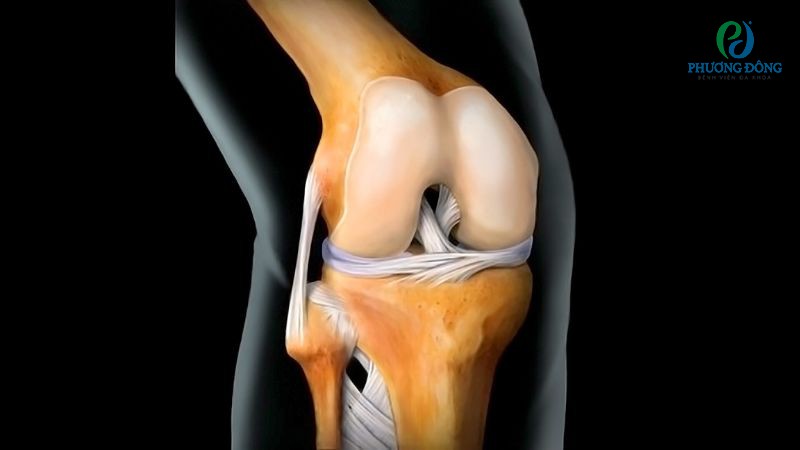

Bao hoạt dịch thường tập trung ở các khớp hoạt động nhiều, phải chịu áp lực lớn và thường xuyên xảy ra ma sát. Trong đó khớp gối, khớp vai, khớp háng luôn có hệ thống màng hoạt dịch đi kèm, hỗ trợ chức năng vận động và bảo vệ mô mềm xung quanh.

Khớp gối

Khớp gối được coi là khớp lớn nhất của cơ thể, chứa tới 11 - 13 bao hoạt dịch. Chúng nằm phân bổ xung quanh xương bánh chè, gân cơ tứ đầu đùi, gân cơ bán gân và một số vị trí khác.

Màng hoạt dịch ở khớp gối đóng vai trò như chất bôi trơn, giúp chuyển động khớp gối trở nên mượt mà hơn. Bộ phận này còn được coi như miếng đệm chống sốc, giảm lực tác động lên xương ống chân khi thực hiện các hoạt động chạy nhảy.